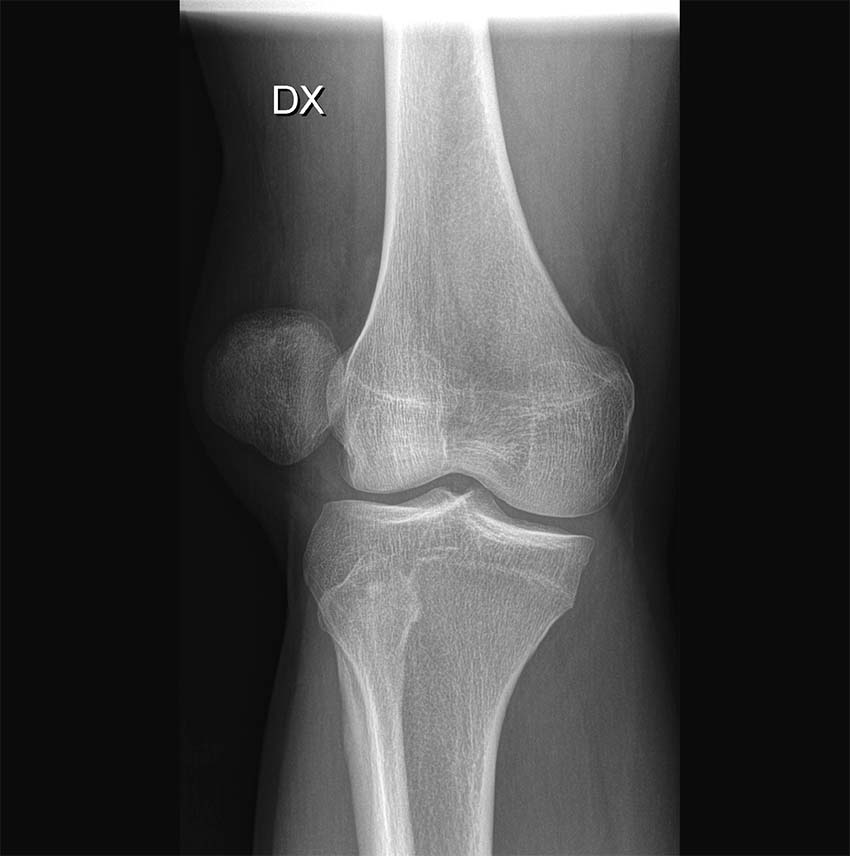

Slätröntgen

Slätröntgen av knät bör omfatta tre projektioner: anteroposterior, lateral med knät i 30 graders flexion samt femoropatellär vy (Merchants vy) [11]. Subluxation, patellar tilt och trochleadysplasi värderas med Merchants vy, medan patella alta bedöms lättast med den laterala vyn.

Bilddiagnostisk undersökning i det akuta skedet är nödvändig för att kunna bedömma helhetsbilden och utesluta både fraktur samt fria osteokondrala fragment. Slätröntgen bör tas i tre olika plan: anterioposteriort, lateralt samt femoropatellärt. Detta för att kunna utvärdera den patellofemorala leden samt, om möjligt, upptäcka skelettskador/andra abnormaliteter.

I vissa fall kan osteo­kondrala fragment identifieras med slätröntgen. Notera ett halvmåneformat fragment strax inferiort om patella.